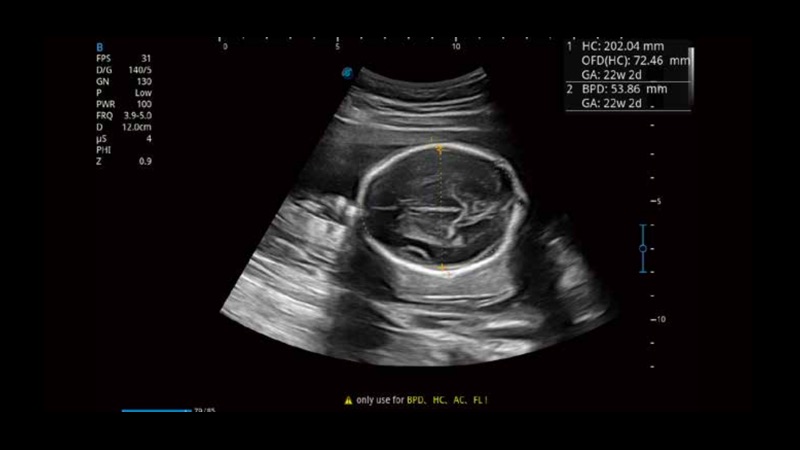

Based on a big data dependable deep learning algorithm, S-Fetus is a brilliant one-step solution for automatic standard plane acquisition and measurement. With just one click, common fetal biometry results are obtained with high intelligence, accuracy and efficiency, aiming for an unprecedented ease during operation.

Less keystroke required while achieving more sensitive and advanced automated common fetal biometry.